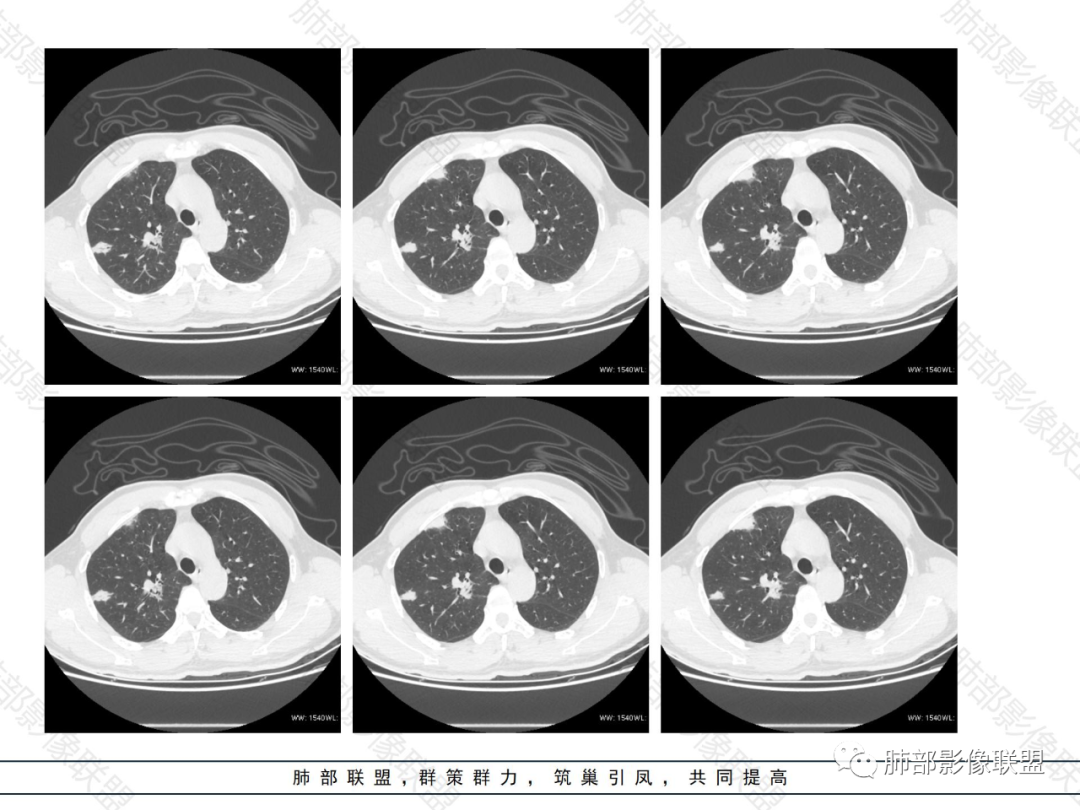

1.病灶分布:因为肺内淋巴瘤主要侵犯对象是肺间质和支气管黏膜下组织,病灶主要位于在沿支气管血管束分布、肺间质及胸膜下,病灶可跨叶分布。

2.病灶的密度:密度均匀,部分病灶内可见空洞及气液平,轻中度均匀强化。

3.支气管充气征伴或不伴支气管扩张:肿瘤细胞沿肺间质及支气管黏膜下组织浸润,支气管管壁未见明显破坏,管腔内未见肿瘤细胞充填,呈现充气支气管征;充气支气管走行自然,无扭曲、僵硬,内壁管腔光滑,支气管管壁见增厚并常有管腔的扩张,含气支气管可呈串珠样不均匀扩张,扩张明显处呈空腔样或皂泡样的囊状含气影;支气管扩张目前有两种意见:一是由于肿瘤组织起源于肺间质,肿瘤沿或跨越脏器解剖结构生长,原有解剖结构残留,周围增生的纤维结缔组织牵拉导致支气管扩张;二肿瘤侵犯支气管粘膜下植物神经丛致平滑肌张力丧失;而这类支气管扩张在肿瘤治疗后有时可消失。

支气管充气征伴扩张

4.血管造影征:肿瘤组织浸润引起间质增厚、肺泡壁破坏、肺泡腔充填,而周围充盈血管走行自然,未受肿瘤侵犯。血管造影征

5.病灶的边缘:有膨隆,浅分叶,也有平直、收缩,平直收缩是因为肿瘤组织浸润致肺泡塌陷及周围纤维组织增生,牵拉正常的肺组织向病灶中心形成聚拢状改变,似呈“炎性”改变。

膨隆、平直

6.间质性改变:多位于病灶周围,可见边缘磨玻璃密度影或晕征及树芽征象,周围组织间质增厚并且有结节感,病理基础为肿瘤细胞浸润细支气管周围间质及肺泡壁。

磨玻璃影及间质小结节影